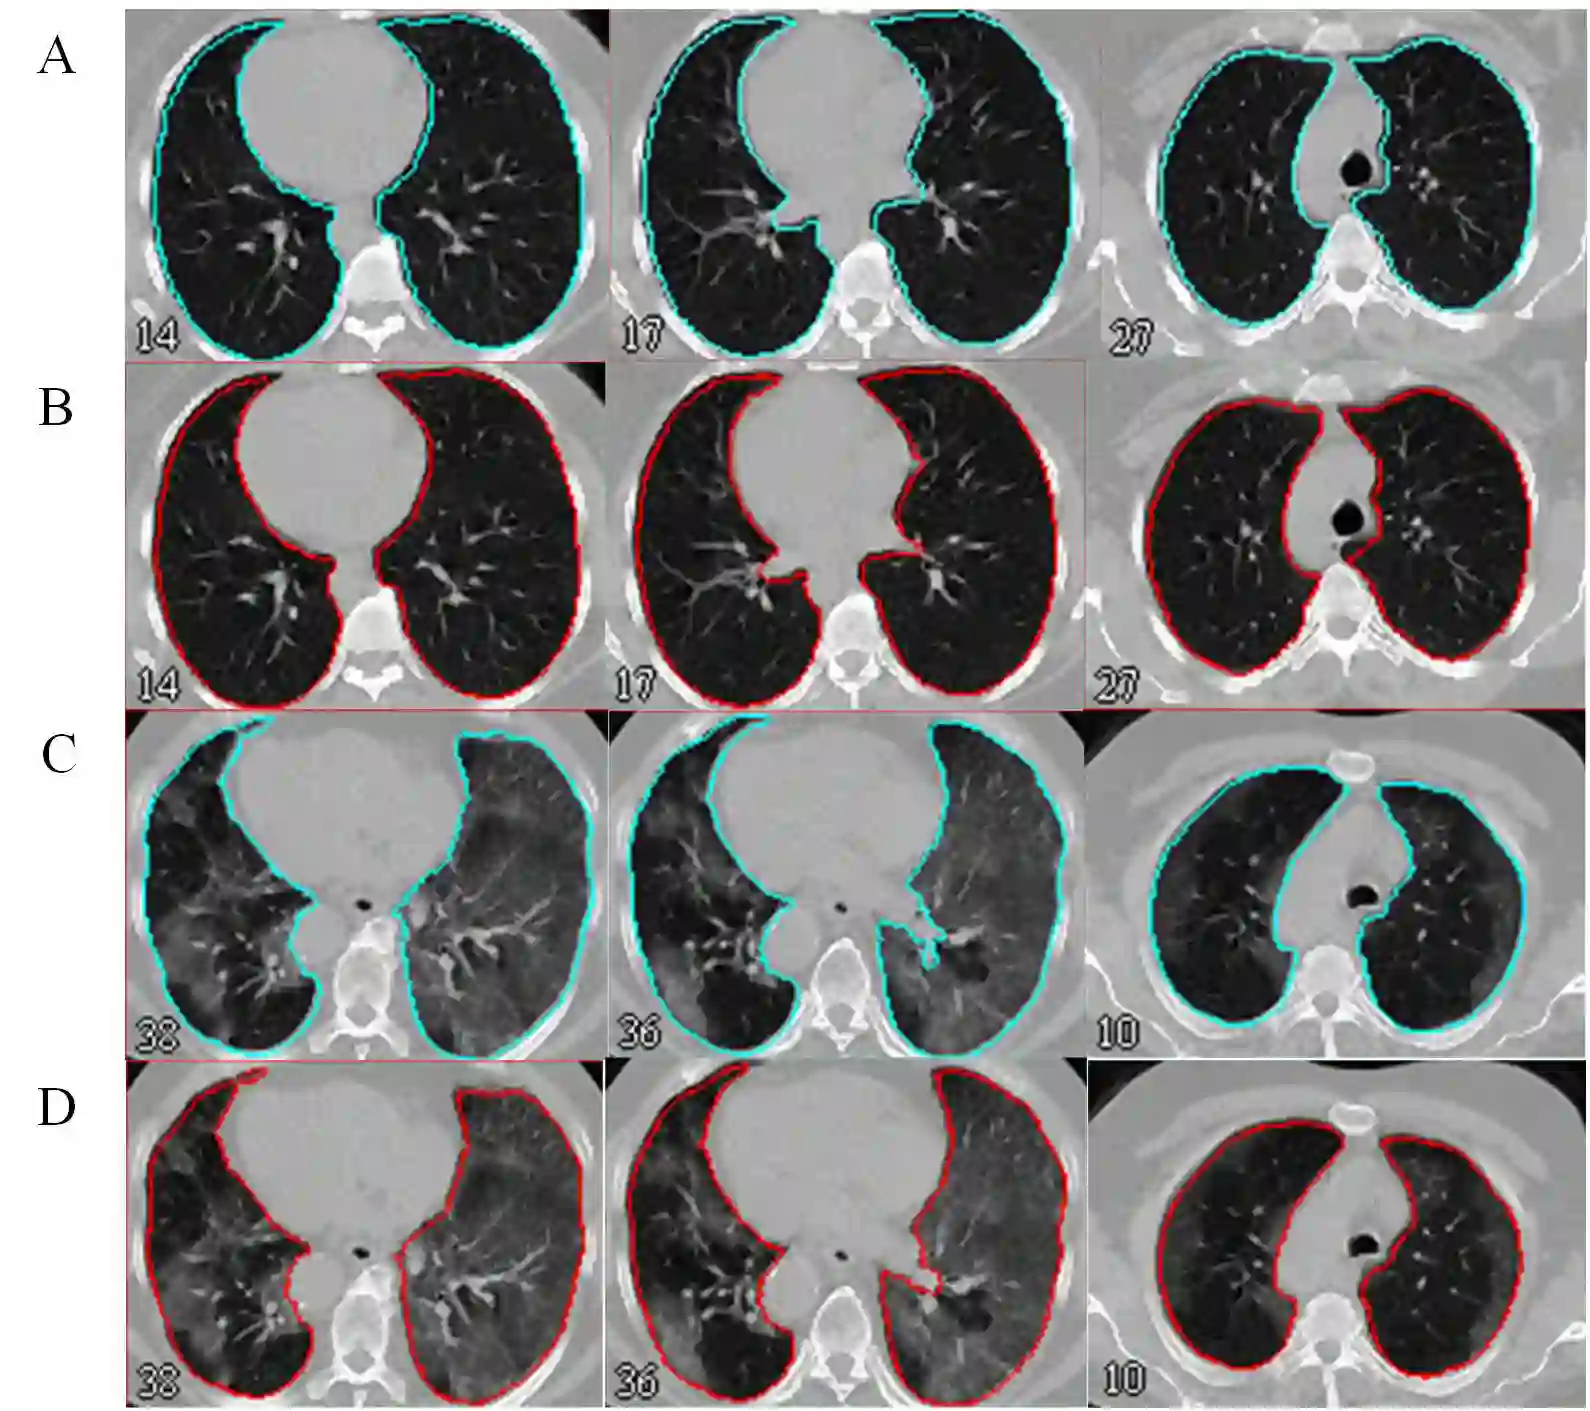

Automated semantic image segmentation is an essential step in quantitative image analysis and disease diagnosis. This study investigates the performance of a deep learning-based model for lung segmentation from CT images for normal and COVID-19 patients. Chest CT images and corresponding lung masks of 1200 confirmed COVID-19 cases were used for training a residual neural network. The reference lung masks were generated through semi-automated/manual segmentation of the CT images. The performance of the model was evaluated on two distinct external test datasets including 120 normal and COVID-19 subjects, and the results of these groups were compared to each other. Different evaluation metrics such as dice coefficient (DSC), mean absolute error (MAE), relative mean HU difference, and relative volume difference were calculated to assess the accuracy of the predicted lung masks. The proposed deep learning method achieved DSC of 0.980 and 0.971 for normal and COVID-19 subjects, respectively, demonstrating significant overlap between predicted and reference lung masks. Moreover, MAEs of 0.037 HU and 0.061 HU, relative mean HU difference of -2.679% and -4.403%, and relative volume difference of 2.405% and 5.928% were obtained for normal and COVID-19 subjects, respectively. The comparable performance in lung segmentation of the normal and COVID-19 patients indicates the accuracy of the model for the identification of the lung tissue in the presence of the COVID-19 induced infections (though slightly better performance was observed for normal patients). The promising results achieved by the proposed deep learning-based model demonstrated its reliability in COVID-19 lung segmentation. This prerequisite step would lead to a more efficient and robust pneumonia lesion analysis.